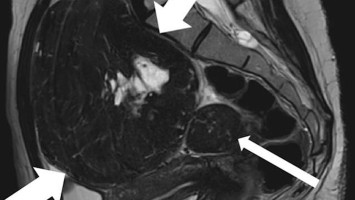

Multiple Raumforderungen beider Ovarien – und ein auffälliger Hautbefund

Eine 21-Jährige Nulligravida stellt sich mit Unterbauchschmerzen vor. Der Befund: multiple rezidivierende Raumforderungen beider Ovarien sowie ein benigner Hauttumor an der Nase. Bereits mit 16 wurden beidseitig benigne Ovarialtumoren entfernt. Wie würden Sie diesen komplexen Fall diagnostisch und therapeutisch einordnen?

e.Med Interdisziplinär Icon, Search Icon, Transvaginaler Ultraschall/© Graphicroyalty / stock.adobe.com (Symbolbild mit Fotomodellen), Glaszellentumor der Gebärmutter/© Boeker M et al. / all rights reserved Springer Medizin Verlag GmbH, Extrauteringravidität /© Tsitlakidis I et al. / all rights reserved Springer Medizin Verlag GmbH, Bilaterale ausgedehnte zylindrische Bronchiektasen/© Düsterhöft D et al. / all rights reserved Springer Medizin Verlag GmbH, CT des Uterus einer 47-Jährigen /© Rizos A et al. | all rights reserved Springer Medizin Verlag GmbH, MRT des Beckens: Uterus und Ovarialtumoren/© Hosten AK et al. / all rights reserved Springer Medizin Verlag GmbH, Digitales Blutdruckmessgerät/© Kotchakorn / Stock.adobe.com (Symbolbild mit Fotomodell), Frau tastet ihre Brust ab/© Pheelings Media / Getty Images / iStock (Symbolbild mit Fotomodell), Feten von siamesischen Zwillingen/© Zahn E et al. / all rights reserved Springer Medizin Verlag GmbH, MRT einer intrakavitären Raumforderung/© Lattermann M et al. doi.org/10.1007/s00761-025-01733-0 unter CC-BY 4.0, Aufnahme nach Resektion der Extrauteringravidität/© Antonia Jörger